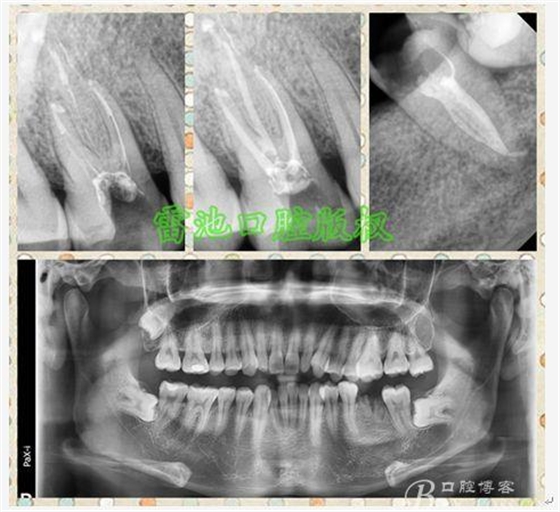

H、關(guān)于下磨牙MM根管的重視問(wèn)題:

備注:為了更好的講解《根管治療的那些事兒(下)》(包括根管清理預(yù)備,沖洗,封藥,充填等問(wèn)題),結(jié)合我這基層小診所的設(shè)備,我個(gè)人歸納總結(jié)一下除了以上某些小材料與設(shè)備,一般還需要準(zhǔn)備如下設(shè)備與材料,相信會(huì)對(duì)大家提高自己的根管治療水平和效率有所幫助:

1、根管測(cè)量?jī)x與電活力測(cè)定設(shè)備應(yīng)該也是必備的: